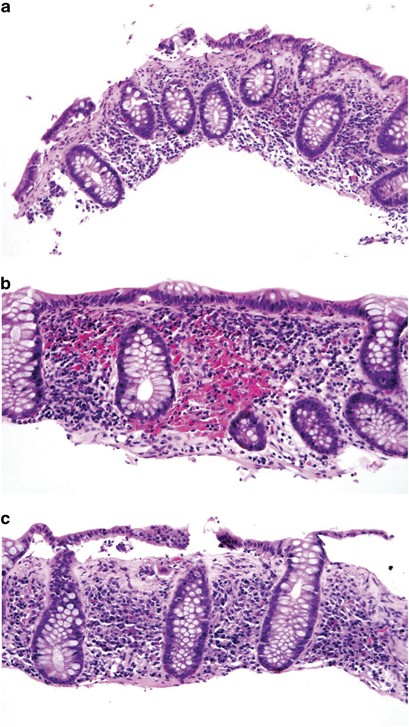

All patients had typical histologic features of CC including a combination of lymphoplasmacytic infiltration of the lamina propria, surface epithelial injury, surface intraepithelial lymphocytosis, and thickening of subepithelial collagen plate (Figure 1). Two patients (of 7, 29%) were diagnosed on biopsies taken from sigmoid–rectal and descending/sigmoid/rectal regions. The remaining five patients (of 7, 71%) had multiple biopsies throughout the colon and rectum. Among these five cases, biopsies from the colon showed typical features of CC in all 5; four patients also had rectal biopsies at their initial presentation and two had CC on rectal biopsy, but one of the four had a rectal biopsy with only increased intraepithelial lymphocytes but no increase in collagen and one had a normal rectal biopsy.

Histologic features of collagenous colitis. (a) Surface epithelial injury and intraepithelial lymphocytosis, thickening of subepithelial collagen table (H&E stain, 100 × ). (b) Increased lamina propria inflammation and intraepithelial lymphocytosis (H&E stain, 200 × ). (c) Focal sloughing of surface epithelium and thickening of subepithelial collagen table (H&E stain, 200 × ).

The histologic findings of pediatric CC in colorectal biopsies are shown in Table 2. The mean number of surface intraepithelial lymphocytes was 37 per 100 epithelial cells (s.d. 24). Overall, 23 (of 25, 92%) biopsies had surface intraepithelial lymphocytosis (defined as >20 intraepithelial lymphocytes per 100 surface epithelial cells). The mean number of crypt intraepithelial lymphocytes was 10 per 100 crypt epithelial cells (s.d. 7). In addition, 22 (of 26, 85%) biopsies had increased chronic inflammation in the lamina propria and 25 (of 26, 96%) biopsies had surface epithelial injury ranging from mild-to-severe injury including surface denudation. A thickened subepithelial collagen plate with a ‘dripping’ appearance was noted in 24 (of 26, 92%) biopsies from 4 (of 4, 100%) patients, with the absence of the increased collagen in the rectal biopsies in two patients (but these two had increased collagen in more proximal biopsies). Focal crypt distortion was noted in two biopsies (8%) from two patients (of 4, 50%). Focal neutrophilic inflammation (either involving crypts or lamina propria) was noted in two biopsies (of 26, 8%) from two patients (of 4, 50%).